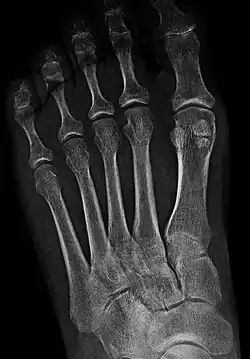

- In the foot—the first metatarsal bone usually has two sesamoid bones at its connection to the big toe (both within the tendon of flexor hallucis brevis).[10] One is found on the lateral side of the first metatarsal while the other is found on the medial side. In some people, only a single sesamoid is found on the first metatarsal bone.